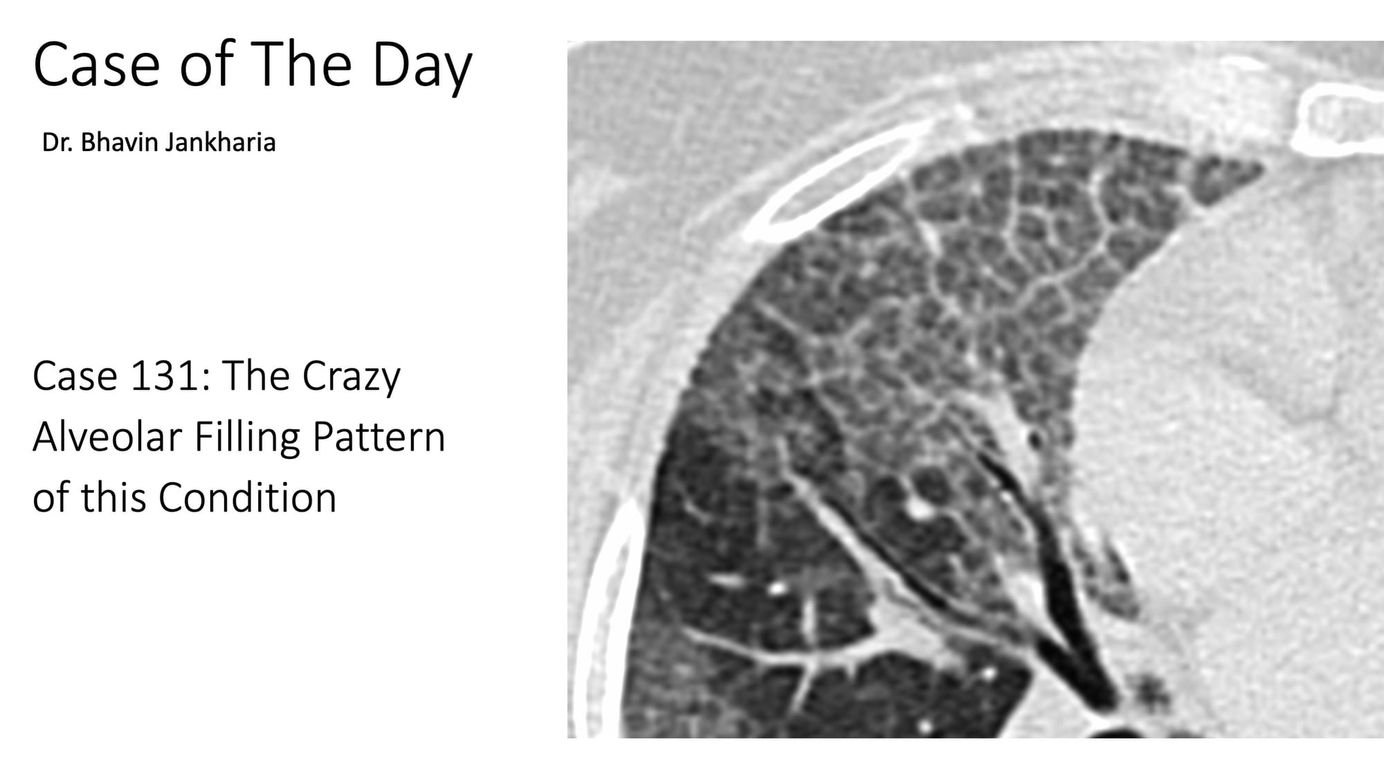

COD 131 - The Alveolar Filling Pattern Members Public

The diffuse crazy-paving pattern is quite distinctive in its classic, typical form.